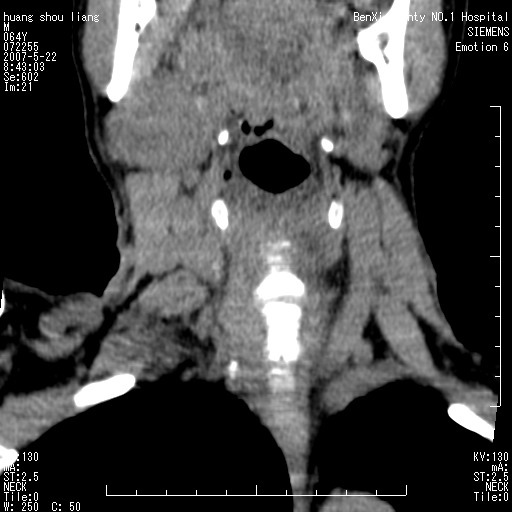

男性,64岁。颈部包块8年。最近增大。

对不起大家,可能是片子发太多有点乱,正常腮腺在下颌角的外侧,颌下腺在下颌体的中部内侧,本例在下颌角内侧偏下,和腺体一点关系都没有,从vrt和mpr上可以很明显看出来,再者肿块是好多粘连在一块的,大家在仔细看看,左侧可能也是吧,我还是考虑为肿大的淋巴结融合在一块,但性质??????

右侧腮腺下部均匀软组织密度肿块,外形不规则,与周围组织分界清晰,考虑右侧腮腺混合瘤或多形性腺瘤。

大家好,病理结果出来了,如大家所说,颌下腺混合瘤。

唉,解剖没学好吧,我诊断错了,不过还是有些不理解回去我在多看看书,谢谢大家的参与,以后我还会奉献好的病例。